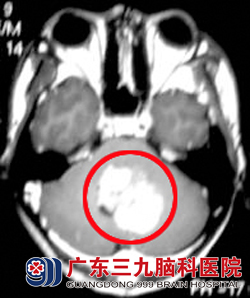

术后行头部及脊髓放疗并辅助化疗,过程顺利。治疗后司徒行走步态平稳,无特殊不适。定期随访均未见肿瘤复发。目前随访8年,司徒状态良好,无肿瘤复发征象,如正常人生活。www.999brain.com

治疗前。 治疗8年后复查。